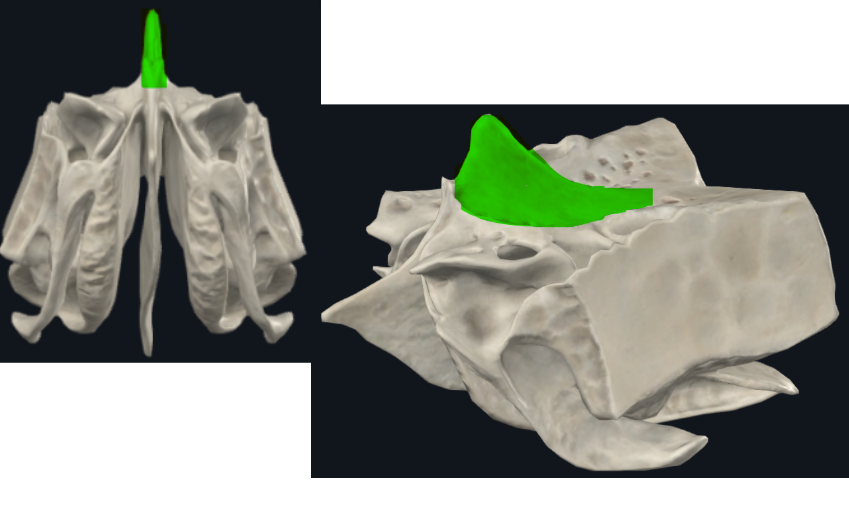

Lámina vertical del etmoides

Lámina perpendicular del etmoides

Forma parte del tabique de separación de ambas fosas nasales (septum/tabique nasal)

Apófisis crista galli por arriba de la lámina horizontal

Apófisis crista galli

Triangular, borde anterior bajo articula con el hueso frontal y completan el agujero ciego(foramen cecum) entre surcos